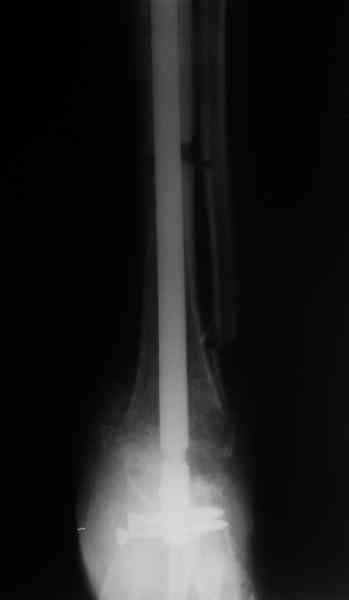

Аппарат был снят окончательно только после введения стержня, то есть оставалось по одной спице в проксимальном и дистальном метафизах большеберцовой кости, спицы в пятке. Фото во время рассверливания в приложении.

ВМ> 1.Необходимость рассверливания была обусловлена проведением

ВМ> стержня через регенераты или зону артродеза,

И то, и другое нужно, это даже не рассверливание, а формирование канала. А рассверливание - подготовка канала под стержень выбранного диаметра, в данном случае 12 мм.

ВМ> возможно ли проведение стержня через регенерат без рассверливания?

Если дистракция была недолго, и делать рано после ее завершения, то можно. В этом случае через верхний регенерат уже бы не получилось.